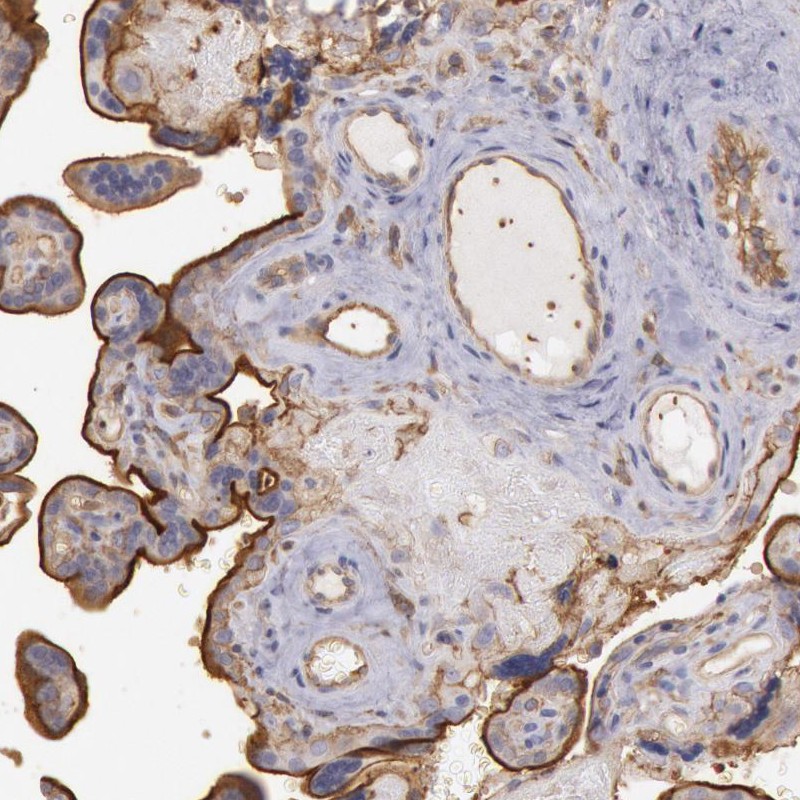

Immunohistochemical staining of human placenta shows strong membranous positivity in trophoblastic cells.